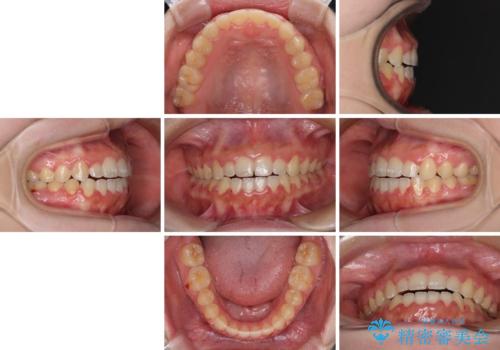

- 前歯のデコボコと、下顎の変位と受け口を気にして来院された患者様です。

初診時には大学病院にて顎の骨を切る外科矯正を勧めましたが、妥協的なゴールでも構わないので外科処置をせずに矯正を行いたいとのことでした。

まずは急速拡大装置にて上顎骨を側方に拡大し、インビザラインにて歯列と咬合を整えることとしました。

インビザラインでの治療が困難な場合には、ワイヤー矯正にて仕上げる可能性があることを予めご了承いただきました。

上顎骨を拡大したことで、下顎の歯列を上顎が受け入れられるようになりましたが、インビザラインでは咬み合わせを改善させることができなかったため、ワイヤー矯正にて仕上げることとしました。

ワイヤーを使用したものの、上下前歯のオープンバイトがなかなか改善されませんでしたが、患者希望により治療終了となりました。